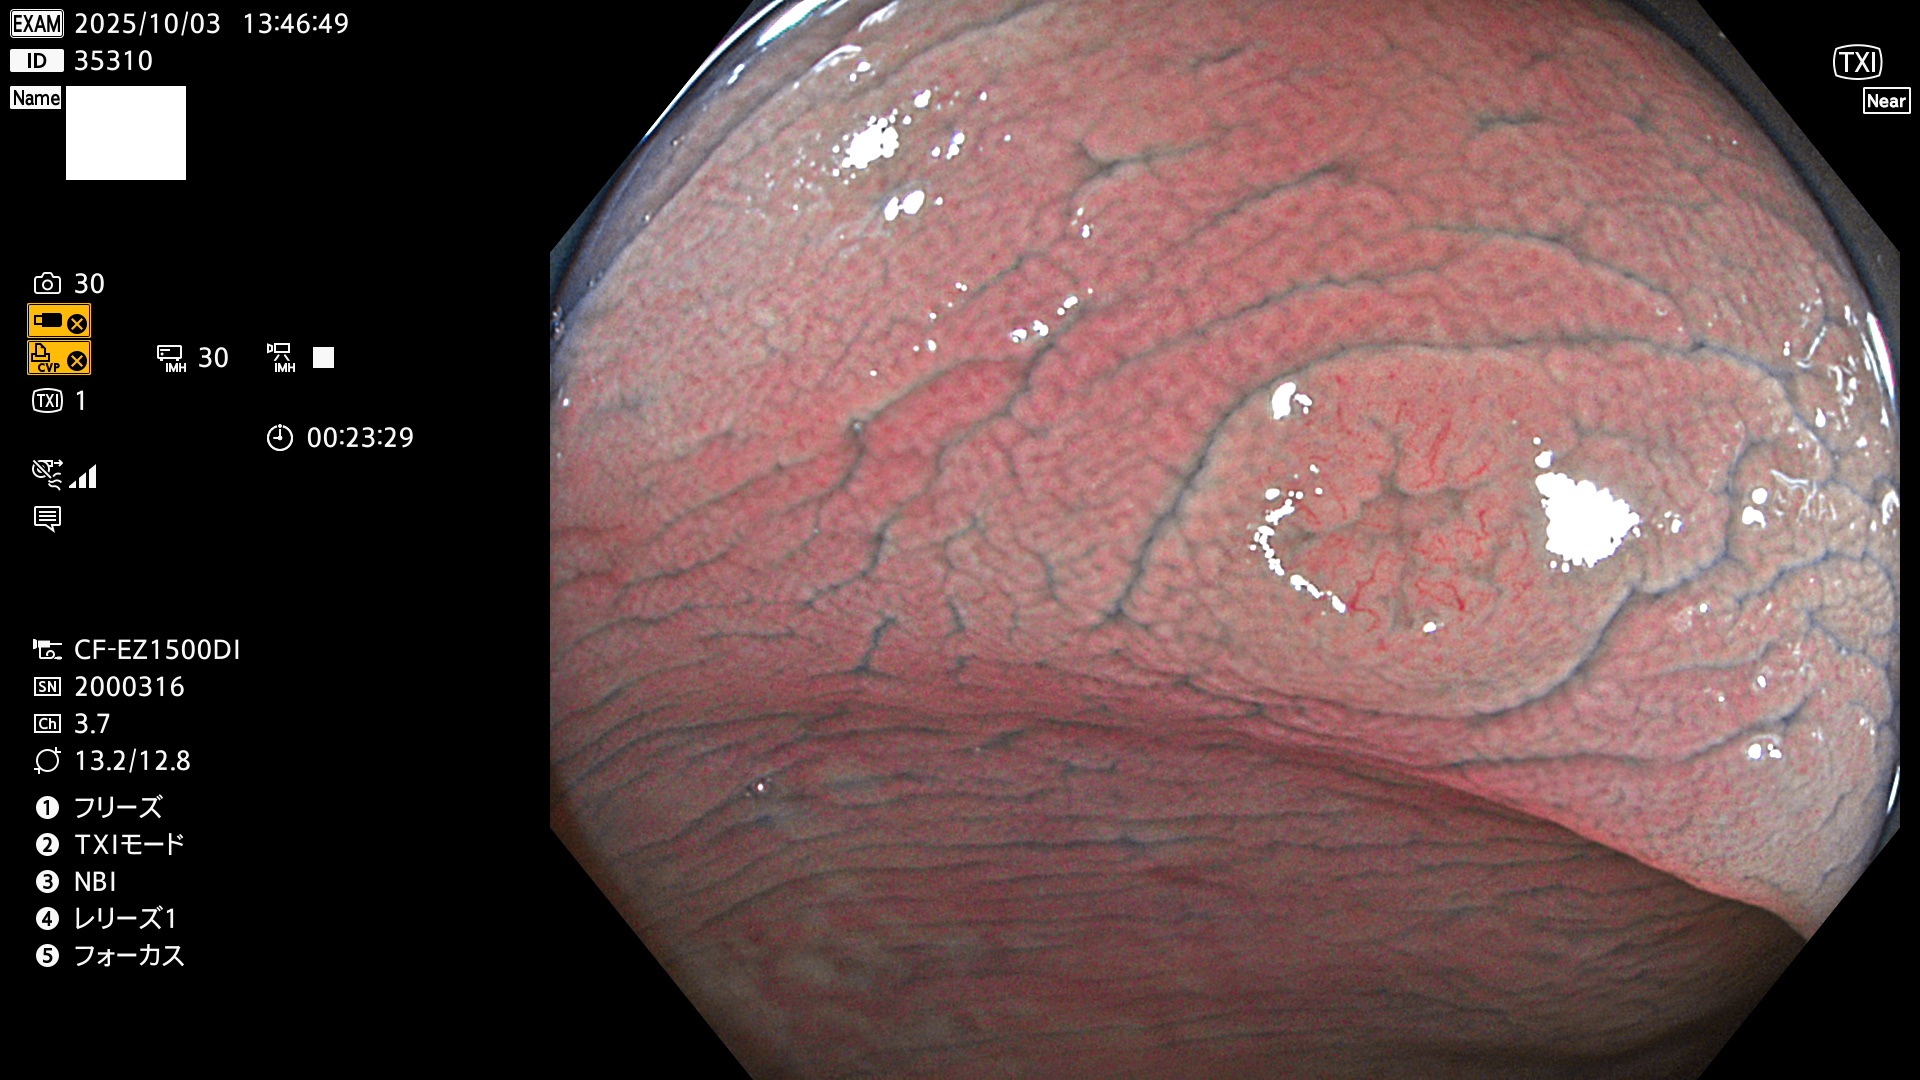

完全に平坦な物をUb、陥凹している物をUcと呼びます。Ubは認識が困難で、Ucはびらん(炎症)と紛らわしいために見落とされやすく、「内視鏡後・大腸癌」の原因になります。

専門的)Uc=De Novo癌? 内視鏡の解像度が低かった時代、このような説もありました。しかし今日の高精度内視鏡では良性の微小なUc型腺腫(APC遺伝子異常の腺腫)が日常的に見つかります。Ucこそが多段階発癌(Adenoma-Carcinoma Sequence)のMain Routeです。

毎週の検査(木・金・土・日)に発見されたUbとUc型・腺腫を、その週の日曜の夜にUPし1週間、提示します。

2025年10月2日〜10月5日の4日間(40件)9個 (Uc_ADR=9個/40人=23%)